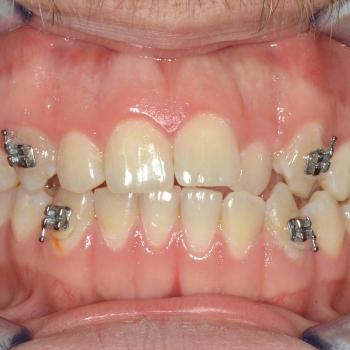

János egy másik fogorvos által befejezett, illetve később részlegesen újrakezdett fogszabályozó kezelés sikertelensége miatt keresett fel rendelőmben. Az első konzultáció alkalmával több esztétikai és funkcionális hibát is észrevettünk, többek között keresztharapást, enyhe nyitott harapást, torlódást, egyoldali Class II harapási eltérést, az alsó és felső őrlőfogak egymással nem harmonizáló dőlését, illetve az alsó középvonal funkció közbeni eltolódását balra.

A kezeléshez János hagyományos fém fogszabályozót választott, melyet kiegészítettünk a legkülönfélébb intermaxilláris gumihúzásokkal, illetve egy speciális belső oldali fogszabályozó ívvel, ami segített az alsó őrlőfogakat a nyelv irányába dönteni.

János kitartásának hála a kezelés végén tökéletes esztétikai és funkciós eredményt értünk el.